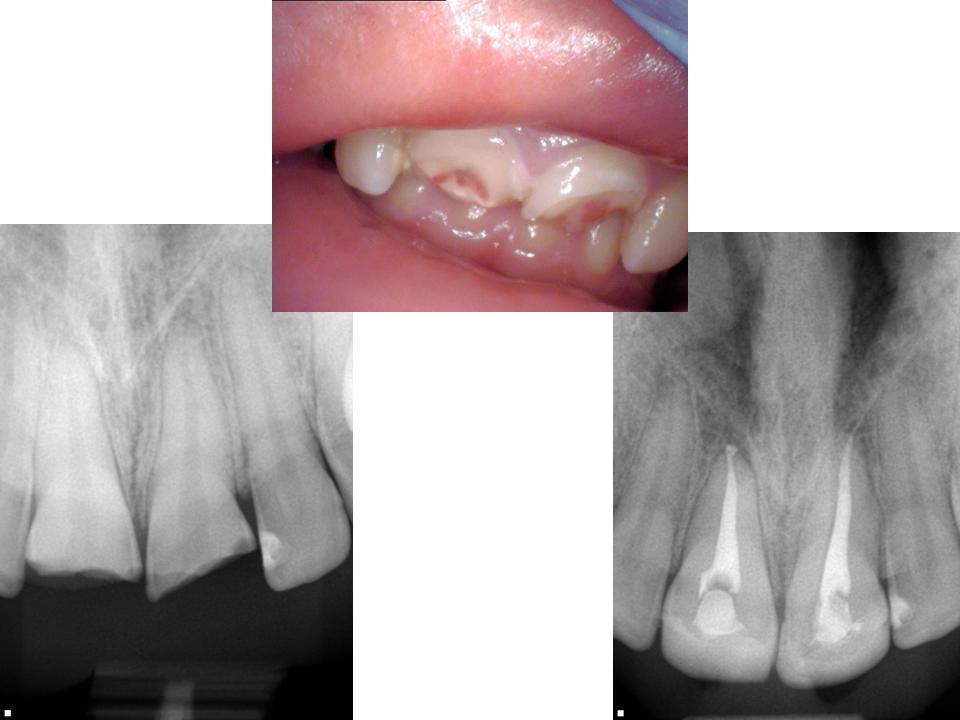

Crown fracture with pulp involvement.

Crown fracture clipart free download! Technically the minimum occlusal reduction is 0.5 mm, but 1 mm is ideal. Involves enamel, dentin, and pulp and can extend below the gumline. Crown fractures are the most common injury to the permanent dentition and may present in several it should not require treatment except adequate testing of pulpal vitality.14 fractures extending into. Zirconia crown fracture due to poor prep design. Crown fracture clipart free download! Complicated crown fracture clinical appearance: Both socially and psychologically, so immediate treatment should be. Download crown fracture images and photos. This kind of traumas may affect the patient. Crown fracture with minimal pulp exposure treatment objective: A practical approach avdc nomenclature. Fracture of maxillary anterior teeth are the most common form of traumatic injuries. There is a loss of tooth structure but no pulpal. Crown fractures are the most commonly reported dental injuries, characterized by fractures of the enamel (figure 2) or enamel and dentin (figure 3). While a porcelain crown is sturdy enough to last for at least a decade. All teeth are susceptible to fracture, but in the mature dog and cat, maxillary canines are most commonly broken, followed by the mandibular canine.